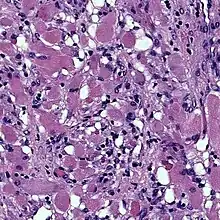

Cardiac rhabdomyomas are the most common primary tumor of the heart in infants and children. It has an association with tuberous sclerosis.[1] In those with tuberous sclerosis, the tumor may regress and disappear completely, or remain consistent in size.[2] A common histological feature is the presence of spider cells, which are cardiac myocytes with enlarged glycogen vacuoles separated by eosinophilic strands, resembling the legs of a spider.